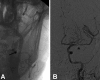

Figure (2):

Figure (2):. Patient with example of tandem occlusion, (A) proximal ICA occlusion (arrow) and (B) MCA occlusion (arrowhead)